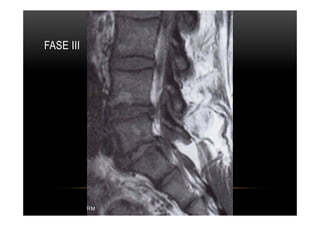

•  Tipo III

•  Alterações caracterizadas por diminuição da intensidade do sinal em T1 e T2 indicando

esclerose reativa que pode, inclusive, ser identificada em radiografias simples.

•  O intenso hipossinal reflete a ausência de tecido medular nas áreas de esclerose óssea

avançada.

•  Apresentação menos frequente que Modic II

MODIC III

PLATÔS VERTEBRAIS •  TipoIII •  Alterações caracterizadas por diminuição da intensidade do sinal em T1 e T2 indicando esclerose reativa que pode, inclusive, ser identificada em radiografias simples. •  O intenso hipossinal reflete a ausência de tecido medular nas áreas de esclerose óssea avançada. •  Apresentação menos frequente que Modic II